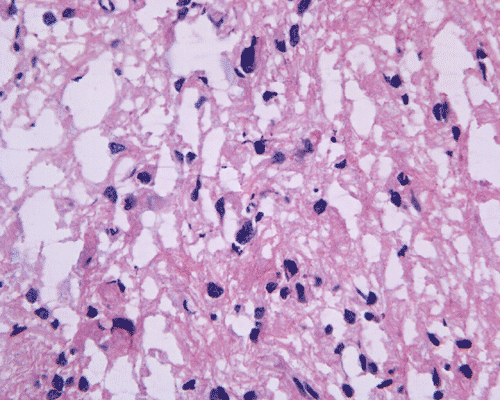

Pathology of the case: A small specimen was obtained by endoscopic biopsy. The specimen cannot be smear out after being squashed and remain as several, large, stellate-shaped cohesive clumps (Panel D). The edges of these clumps are relatively thin and allows better observations. The nuclei do not appear to be pleomorphic. Many elongated cytoplasmic processes can be seen (Panel E) and are suggest a glial nature of these cells. The lesion gives a spongy appearance on low-magnification (Panel F). On medium-magnification, there are some clustering of nuclei (Panel G). On high-magnification, the nuclei appear hyperchromatic and pointy but no substantial pleomorphism, prominent nucleoli, or mitotic figure. Some bluish, mucoid material is identified in some microcysts (Ú in Panel H).

There is no endothelial proliferation or necrosis. An  intraoperative diagnosis of glial neoplasm was made. The lesion was entirely resected. On paraffin section, the lesion has a hypocellular background decorated by many small microcysts, often in clusters, that contain mucoid material and small cluster of nuclei that resemble bundles of flowers (Panel I and J).  The nuclei are bland. There was no mitosis, endothelial proliferation or necrosis (Panel K and L).

Histologically, the tumors are composed of a uniform population of ependymal cells embedded in a densely fibrillar glial matrix; with groups and islands of cells surrounded by acellular bands of glial fibers. Mitoses are rare or absent. Like other ependymal tumors, perivascular coronary arrangements of tumor cells (pseudorosettes) can occur. These arrangements, however, is usually not conspicuous, small, and relatively uncommon. When the amount of pseudorosette is substantial, a diagnosis of ependymoma should be considered seriously. Larger tumors, particularly those arising in the lateral ventricles, often show microcyst formation. Other features include hemosiderin deposition from prior hemorrhages, sclerotic blood vessels and calcifications 9.  Subependymomas have the lowest rate of cell proliferation of ependymal tumors as evidenced by Ki67 (MIB-1) labelling 9 . PET scan study in one case also reveals exceedingly low rates of glucose metabolism and kinetic constants. The hypometabolism indicates low cellular density and slow growth 10.     Ultrastructurally, astrocytic or ependymal cells are seen with transitional forms between these two appearances, demonstrating that the neoplasm is of one cell type. Large cells similar to ependymoglial precursor cells suggest that subependymomas may originate from cells of the adult subependymal layer 11.